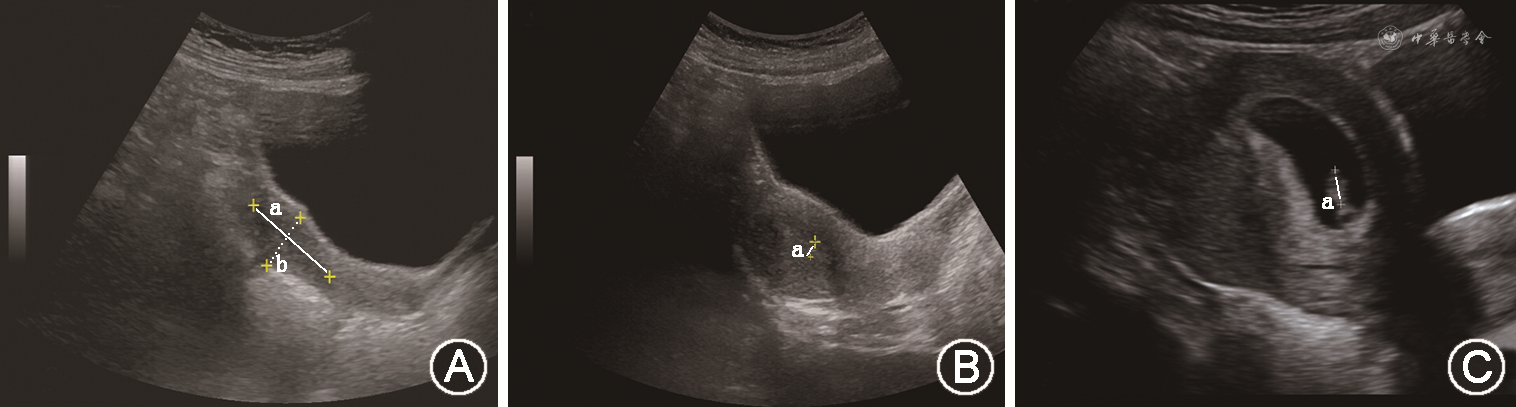

辅助检查:染色体:46,XX;黄体生成素(LH)<0.2 U/L,卵泡刺激素(FSH)<0.2 U/L,雌二醇(E2)<15 μg/L。曲普瑞林兴奋试验:LH峰值为1.2 U/L,FSH峰值为3.63 U/L。其他垂体前叶激素均在正常范围内。经腹子宫及双附件超声结果:子宫大小为3.8 cm×3.3 cm×2.1 cm,内膜厚约0.3 cm;左卵巢大小为2.8 cm×0.6 cm,右卵巢大小为2.2 cm×1.2 cm(图1A)。鞍区MRI提示未见占位性病变。嗅神经MRI可见正常的双侧嗅球和嗅束。

诊治经过:综合患者起病年龄、临床表现、体格检查及实验室检查,患者生物年龄>14岁,尚无青春发育和月经来潮,雌二醇水平低且促性腺激素水平低,无其他垂体前叶激素分泌障碍,无其他慢性系统性疾病,嗅觉正常,临床诊断先天性低促性腺激素性性腺功能减退症(CHH)较为明确。患者自2019年9月起予小剂量雌激素(戊酸雌二醇0.5 mg,1次/d)治疗9个月,后增加其剂量(1 mg,1次/d)治疗6个月,监测患者双乳发育达Tanner分期Ⅴ期,复查经腹子宫及双附件超声提示子宫较前明显增大,为5.2 cm×5.5 cm×3.6 cm(达成年生育期女性子宫大小),且子宫内膜清晰可见(图1B)。随后进行周期性雌、孕激素联合治疗(戊酸雌二醇2 mg,1次/d,连用11 d;戊酸雌二醇2 mg,醋酸环丙孕酮1 mg,均1次/d,连用10 d),连用6个月,期间可有撤退性阴道出血。因患者生育需求强烈,2021年6月开始予脉冲促性腺激素释放激素(GnRH)皮下输注治疗(凯联茵诺®泵ATA-S-1-0型,沪械注准20192140393),戈那瑞林(安徽丰原药业,国药准字:H10960064)脉冲间隔时间为90 min,脉冲剂量为10 μg。治疗1个月后患者否认过敏、活动受限等不良反应,复查LH为1.85 U/L,FSH为1.56 U/L,雌二醇为137 μg/L。治疗40 d后月经来潮,此后每隔30~35 d月经来潮1次,末次月经时间为2021年9月24日。患者治疗19周后监测尿绒毛膜促性腺激素(β-HCG)阳性,血β-HCG>1 050 U/L,经阴道子宫超声提示宫腔内见妊娠囊3.9 cm×4.6 cm×1.8 cm,内见胎芽与胎心搏动(图1C),提示宫内早孕。发现宫内妊娠后(孕6周时),停用脉冲GnRH注射,予黄体酮支持治疗。妊娠期间监测其他垂体前叶激素均处于正常范围内。妊娠25周时完善口服葡萄糖耐量试验:空腹、餐后1 h及餐后2 h血糖分别为5.7、6.5和7.3 mmol/L,诊断为“妊娠期糖尿病”,通过饮食和运动控制血糖,监测血糖控制良好。妊娠40周+2顺产分娩一女婴,身长50 cm,体重3 450 g,新生儿身体状况评分(Apgar评分)10分,幼女外阴无畸形。患者产后正常分泌乳汁,母乳喂养,产后1.5个月随诊LH<0.2 U/L,FSH为0.49 U/L,雌二醇<15 μg/L。整个诊疗过程中,下丘脑-垂体-性腺轴激素水平的变化见图2所示(GnRH脉冲泵治疗前的21个月周期性使用雌、孕激素联合治疗,期间患者外周血LH、FSH、雌二醇及β-HCG的水平无明显变化)。